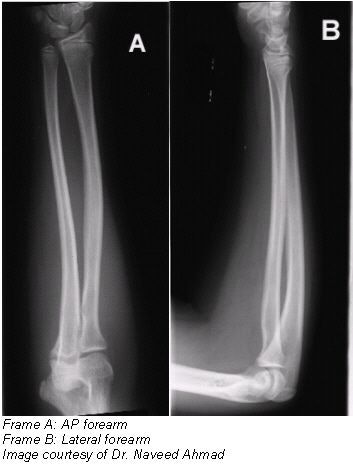

Radiographic examination of the forearm is performed using anteroposterior (AP) and lateral projections. Both projections of the forearm demonstrate the elbow joint, the radius and the ulna, and the proximal row of slightly distorted carpal bones.

- The entire radius and ulna should be visible, with pertinent soft tissues, such as fat pads and stripes of the wrist and elbow joints.

- The wrist (along with the proximal carpal row) and distal humerus should be clearly demonstrated.

- No rotation as evidenced by humeral epicondyles visualized in profile with slight superimposition of the radial head, neck, and tuberosity over the proximal ulna.

- No elongation or foreshortening of the humeral epicondyles.

- Partially open elbow joint if the shoulder was placed in the same plane as the forearm.

- Similar radiographic densities of the proximal and distal forearm.

- Lateral projection of the entire radius and ulna along with wrist and distal humerus should be clearly demonstrated.

- No rotation as evidenced by:

- Superimposition of the radius and ulna at their distal end.

- Superimposition by the radial head over the coronoid process.

- Radial tuberosity facing anteriorly.

- Superimposed humeral epicondyles.

- Elbow should be flexed 90º.

- Pertinent soft tissues, such as fat pads and stripes of the wrist and elbow joints, and bony trabeculations should be visible.